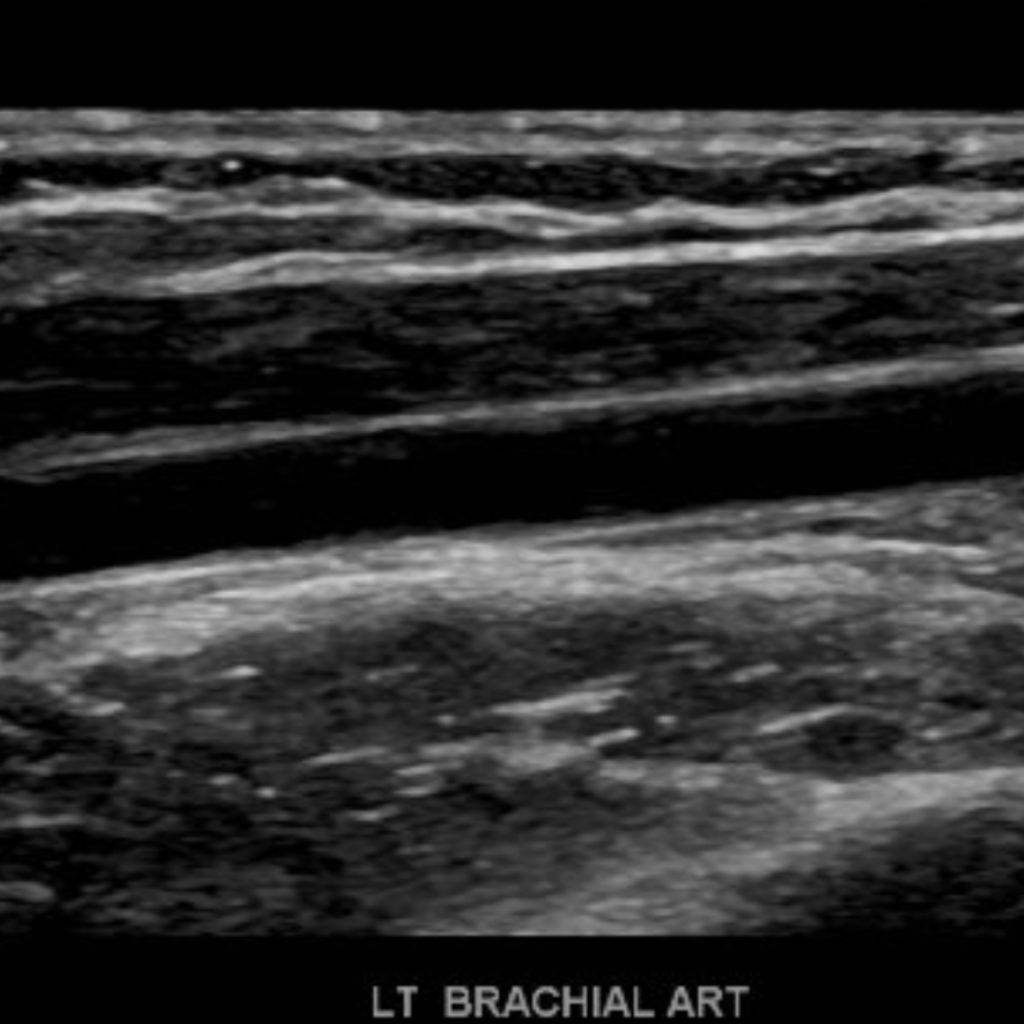

The subclavian artery arises from the brachiocephalic artery on the right and off of the aortic arch on the left. This artery further divides into the axillary, brachial, radial, ulnar, palmar and digital arteries respectively.